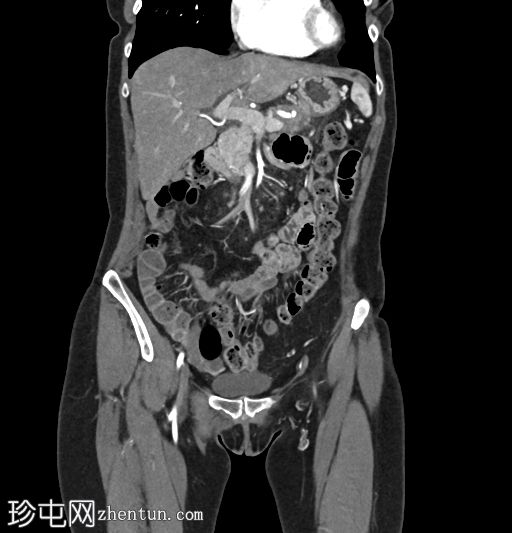

轴位增强扫描

动脉期

术后改变符合慢性胰腺炎Beger手术的影像学表现。胰头显影良好,结构完整;胰尾可见主胰管扩张,系远端胰肠吻合口处浸润性肿块所致。该肿块浸润脾动脉和脾静脉,并伴有血管周围侵犯,以及胰周脂肪浸润。此外,肠系膜可见线状软组织密度影,提示腹膜播散。

左肝叶偶见海狸尾状解剖变异。